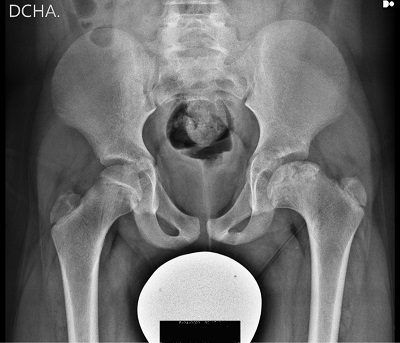

Se inicia seguimiento urgente en la consulta de ortopedia infantil que indica antinflamatorio y descarga de la extremidad. Se realizan controles clínicos y de radiografía seriados con aumento progresivo del apoyo: a los 2 meses se le permite caminar, a los 4 meses correr y saltar dada la importante mejoría (Figura 2).